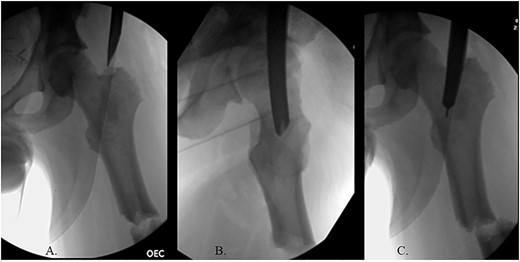

The patient was positioned supine on a fracture table. A guide wire was inserted through a 4-cm surgical incision proximal to the greater trochanter (GT) and was passed through a cannulated awl in a position slightly medial to the tip of the GT on the AP and center on the lateral (Fig. 2B). A (15-mm) entry reamer widened the opening (Fig. 2C). A rigid cannulated reduction rod and forceful malleting allowed the ball-tipped guidewire to cross the close reduced fracture, but too lateral and posterior distally (Fig. 3A and B). The cannulated flexible reamers encountered impassible blastic lesions within the proximal femur (Figs 3C and 5B).

(A) Ball-tipped guidewire slightly lateral position at the knee on the AP XR; (B) ball-tipped guidewire too posterior at the knee on the lateral XR; (C) flexible reamer within the proximal femur abutting blastic lesions.